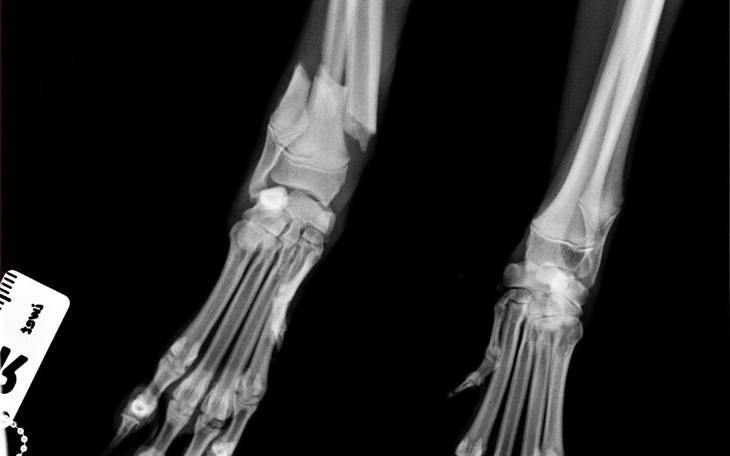

Witam, jestem przyjacielem zwierząt i nie mogę przejść obojętnie wobec cierpienia Azorka. Psina ma około 6 miesięcy i 14 kg, został porzucony wraz z matką i rodzeństwem w lesie na wsi nieopodal Wołczyna. Przygarnięty przez mężczyznę i wychowywany od małego by nie pozwolić trafić mu do schroniska. W nocy 3 lutego doszło do nieszczęśliwego wypadku i Azor ma złamaną przednią łapę, prawdopodobnie przez uderzenie samochodu. Po konsultacjach z wieloma weterynarzami przy takim ciężkim złamaniu operacja będzie droga i kosztować ma 1500 zł! Pieniądze są potrzebne by Azor mógł normalnie chodzić bez bólu. Właściciela nie stać na tak drogą operacje, prosimy o pomoc by psina mogła cieszyć się zdrowiem, które jest dla nas bardzo ważne.